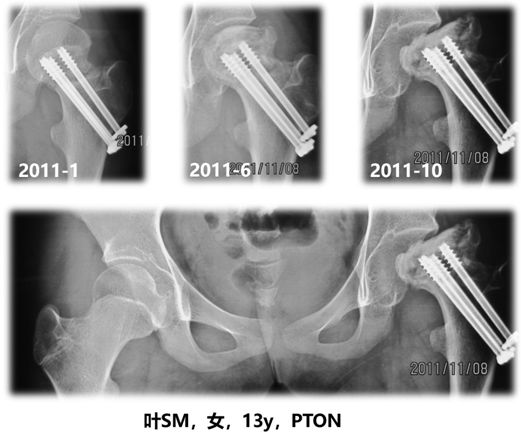

未成年人的股骨颈骨折多由巨大的暴力导致,发生率不及1%。虽然在临床中并不常见,一旦发生股骨颈骨折,多伴随股骨头坏死、骨不连、骨骺早闭、髋内翻等并发症,严重影响患儿的生长发育与生活学习。其中,股骨头坏死是未成年人股骨颈骨折后最为常见的并发症,发病率平均为23%(图1)。由于未成年人股骨近端血运与骨骺发育不全,一旦发生坏死多表现为大面积的坏死,如无有效的干预,必然导致灾难性的后果(图2)。

图1:未成年人股骨颈骨折后股骨头坏死疾病快速进展